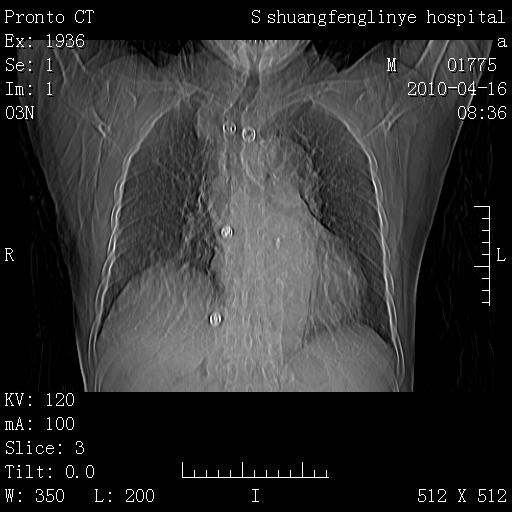

标题: CT25784:咳痰、请会诊!结核? [打印本页]

标题: CT25784:咳痰、请会诊!结核?

老年肺间质纤维化,肺动脉高压-----肺心病。

慢支肺气肿,左上陈旧性结核,主动脉冠脉钙化

1)左肺上叶结核(纤维、增殖病灶)。2)冠状动脉及主动脉钙化。

1)左肺上叶结核(纤维、增殖病灶)。2)冠状动脉及主动脉钙化。肺动脉高压